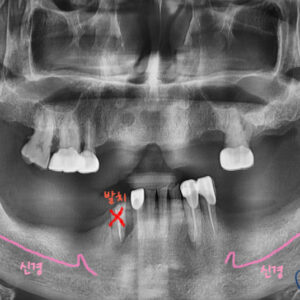

Scan Assist 엔진으로 신경의 위치, 치아의 골조직, 치아와의 거리와 각도 등을

정밀하게 스캔할 수 있다는 장점이 있습니다.